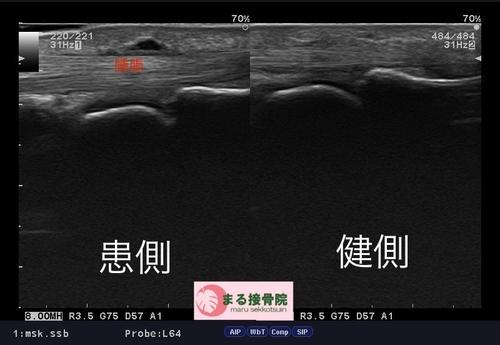

結果、少しガングリオン様の腫瘤が診られ、腱も少し健側に比べると腫れが診られました。

指の付け根の痛み.JPG